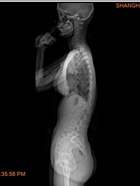

以往案例

我们相信通过专业训练,为您解决脊柱侧凸的困扰,重拾自信,拥有健康挺拔的身姿。

脊柱侧凸又称为脊柱侧弯畸形,是一种复杂的脊柱三维畸形,主要表现为脊柱一个或多个节段向侧方发生弯曲或伴有椎体旋转。侧凸后脊柱常呈现“C”形或者“S”形。